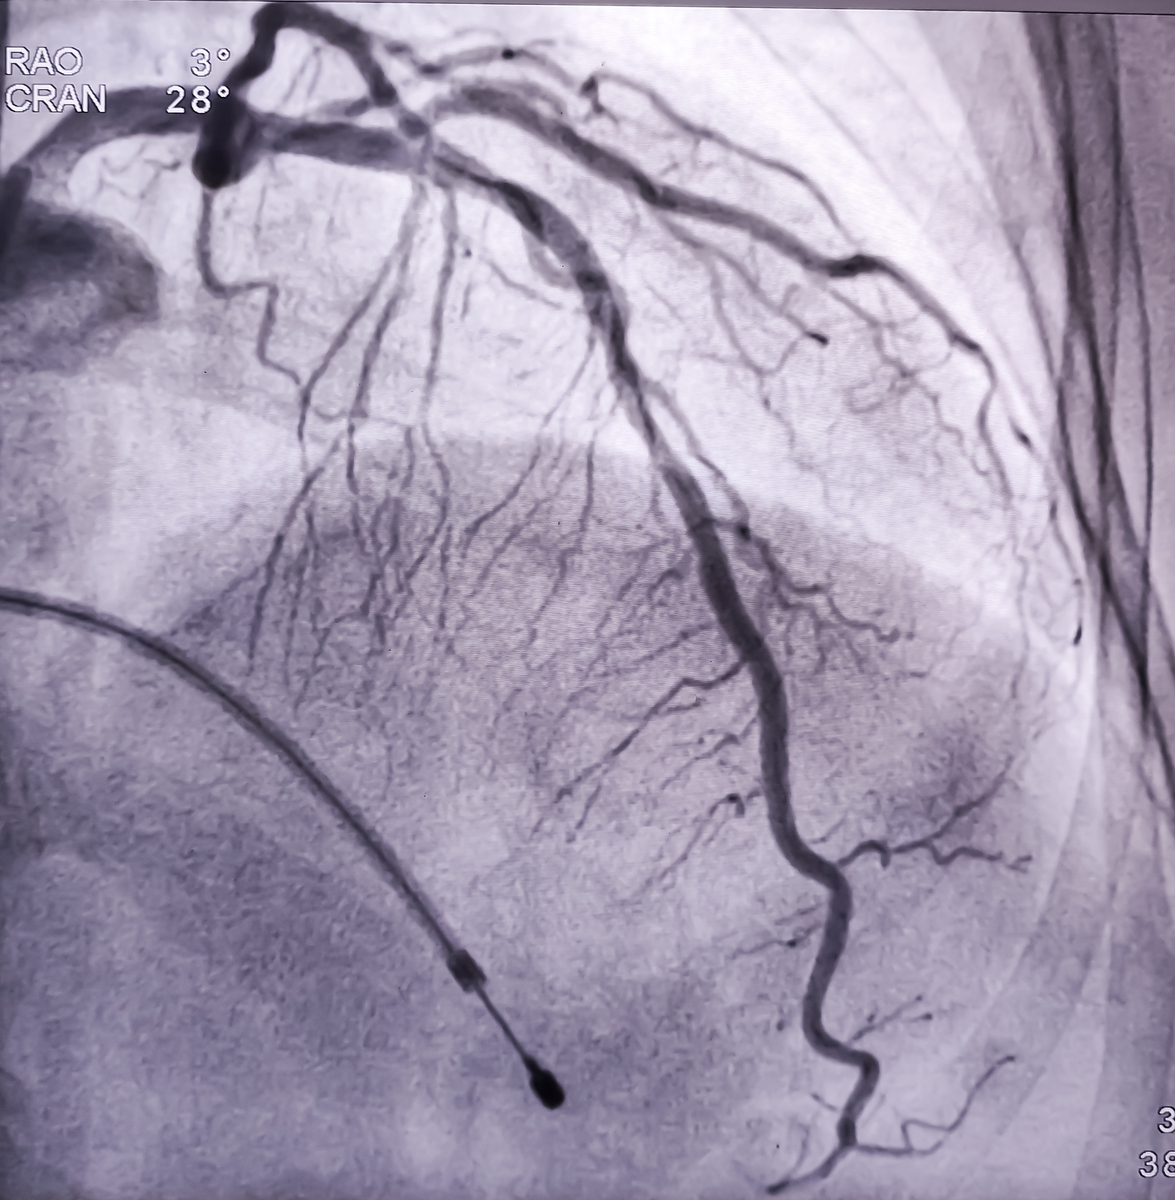

In this case, neovascularization within the carotid artery plaque, plaque ulceration, and floating thrombus were all perfectly visualized by contrast-enhanced ultrasound (CEUS). CEUS accurately identified the cause of stroke as the rupture of the carotid artery plaque leading to thrombus formation. The patient received timely antiplatelet therapy and stent placement, achieving a good prognosis. Therefore, the possibility of vulnerable carotid artery plaque rupture should be considered in acute stroke patients, and contrast-enhanced ultrasound can serve as a new diagnostic approach.